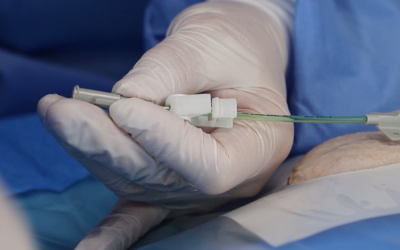

5. Uso del ecógrafo para la punción + Seldinger modificada (imagen 5 A y B):

El ultrasonido aumenta el éxito de punción de la vena al primer intento. Nos permite también tener un control total de la aguja durante la inserción.

Las guías internacionales recomiendan la punción vascular con ecografía y la evidencia ha demostrado que es el modo más seguro y costo-efectivo de realizar la punción. Así mismo, el uso de la técnica de Seldinger modificada (que incluye aguja ecogénica de 21G, pelo en nitinol con punta blanda y microintroductor pelable) permite trabajar en vasos de pequeño calibre como son los del brazo, reduciendo el daño endotelial que pudiera derivarse de la punción venosa e introducción posterior del catéter.